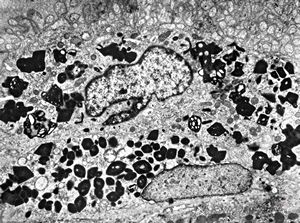

M,5m. | intracellular cholestasis - atresia of biliary ducts

F,2m. | intracellular cholestasis - atresia of biliary ducts